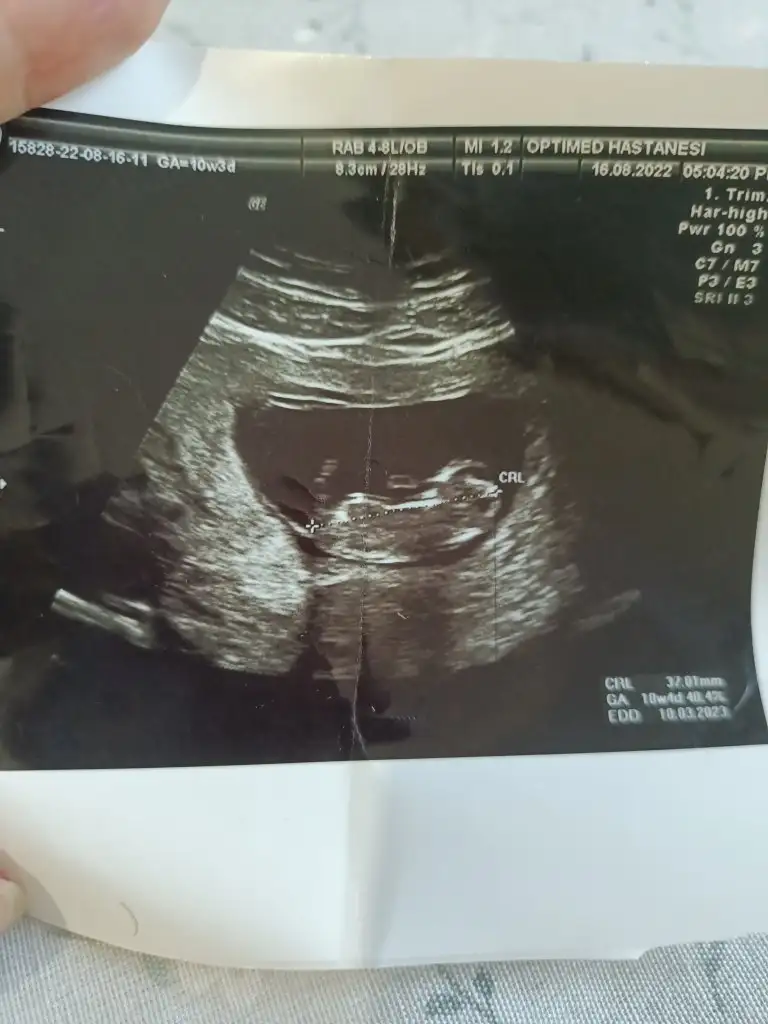

NurSu-14Ocak .!.:Ustteki 9 haftalik

Altakki 8 haftalik

Cok merak ediyorum cinsiyetini